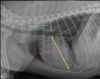

What are the normal characteristics of the feline heart in a lateral view?

A

-heart height is ~ 2/3 of the diameter from dorsal to ventral chest (yellow)

-heart is 2 to 2.5 intercostal spaces wide (pink)

-trachea deviates from spine (blue)